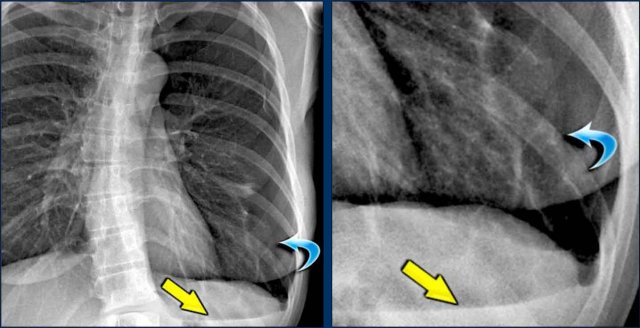

Hidden Areas (3): Pneumonia Below the Diaphragm

In this case, a pneumonia was primarily located below the right diaphragmatic dome (yellow arrow), within the posterior basal segment of the right lower lobe.

• On the lateral view, there is an increase in opacity over the lower thoracic vertebrae, indicating lower lobe consolidation (arrow).

• Again, image magnification may be necessary for adequate assessment.

Hidden Areas (4): Retrocardiac Opacity

Initial review of the CXR reveals a subtle increase in density in the retrocardiac region (blue area), which requires careful attention.

• This was confirmed to be a left lower lobe pneumonia.

• Always correlate with the lateral view, where consolidation in the lower thoracic spine region is a key clue.